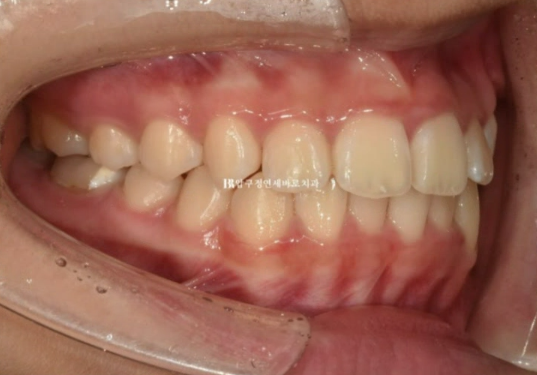

오른쪽 교합은 나쁘지 않습니다.

23.08

왼쪽은 3급 교합관계 때문에 왼쪽 어금니는 잘 안 물리고 이것이 앞니에 영향을 주어 위 앞니 중심이 인중과 얼굴에 비하여 틀어져 있습니다.